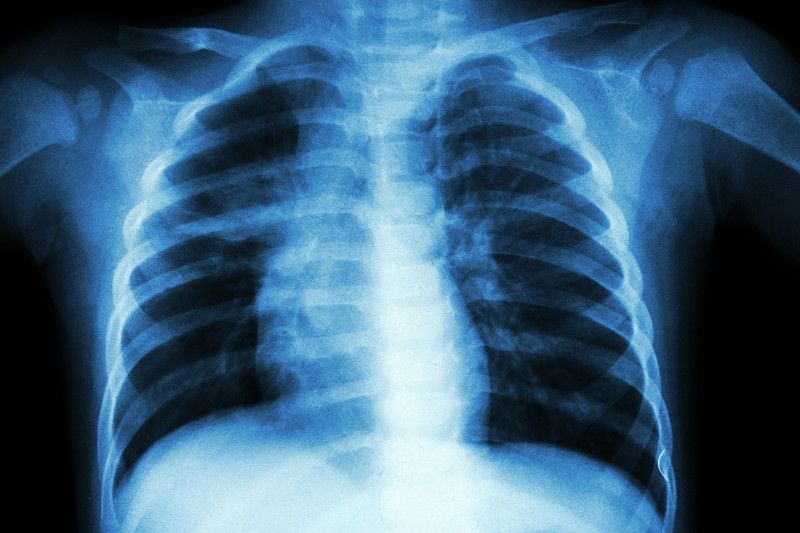

肺结核详情

肺结核详情

肺结核(TB)详情